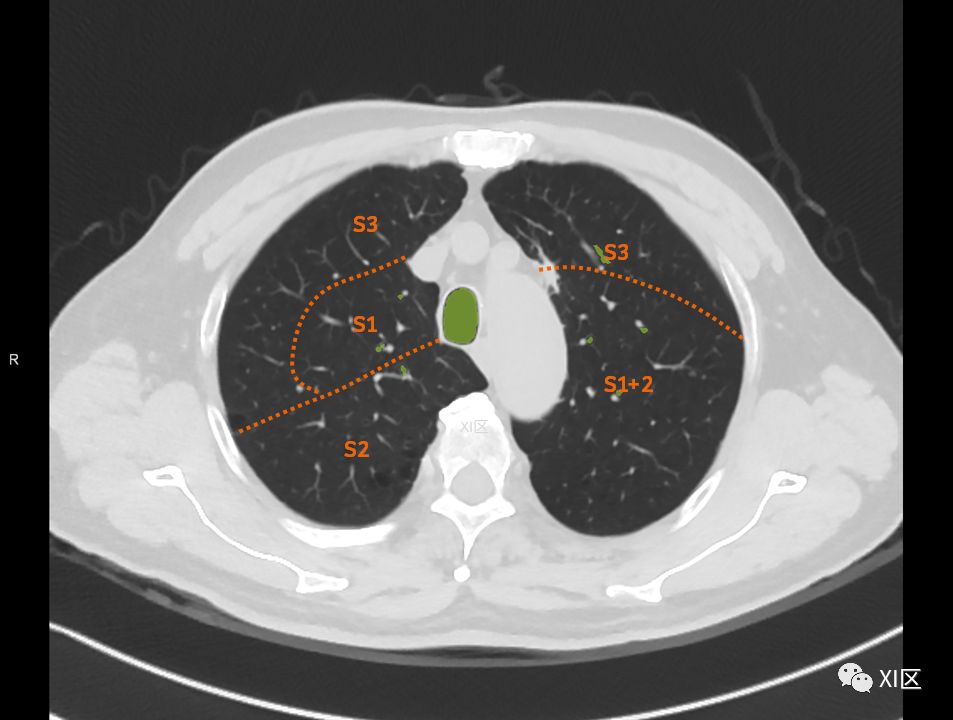

在进行肺的分段时,可以上下观察浏览,沿着相应气管的走形可以更容易准确地进行分段。

肺的断层分段示意图